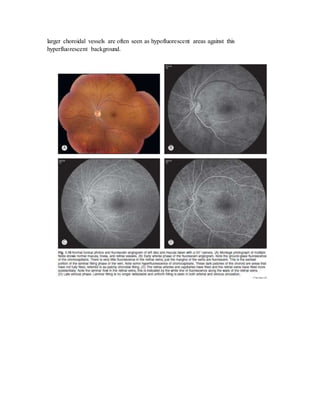

Over the next few minutes, the dye recirculates, with a gradual decline in fluorescence. In

the late phases of the angiogram, the choroid, Bruch's membrane, and the sclera stain. The

larger choroidal vessels are often seen as hypofluorescent areas against this

hyperfluorescent background.